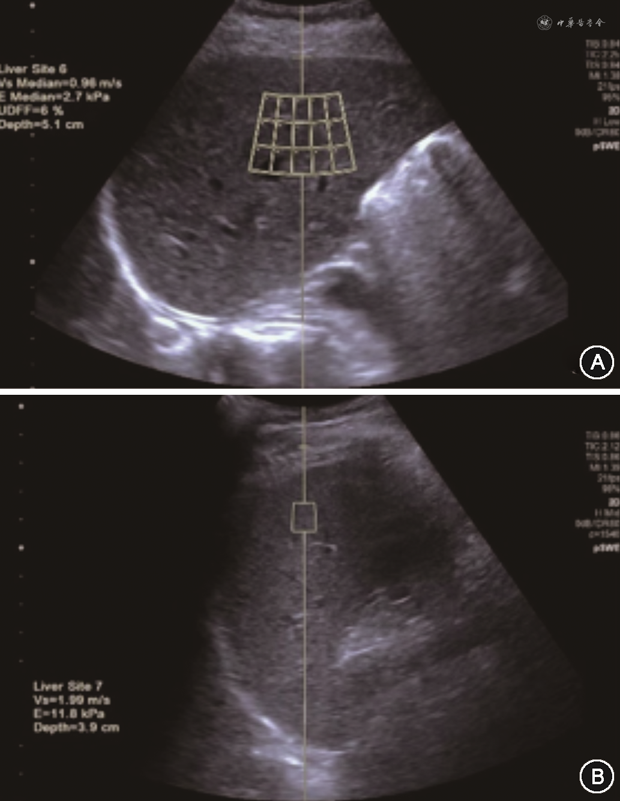

2D-SWE和p-SWE测量时,取样框应置于肝脏实质回声均匀处,避开大血管、胆道及肋骨,取样框尽量平行于肝包膜,放置在肝包膜下方1~2 cm,不超过6 cm处[30, 31, 32,34]。2D-SWE测量LSM时,取样框内填充的彩色信号需超过三分之二,Q-Box优先放置在弹性图的中央位置,建议Q-Box直径≥1.5 cm[31, 32](图1A,图2A)。

(2)测量SSM:被检者仰卧位或轻度右侧倾斜,左臂抬高充分外展,探头垂直于皮肤表面呈90°并适当加压。以灰阶超声图像为基础的p-SWE和2D-SWE测量SSM方法同LSM,取样框尽量平行于脾包膜,放置在脾包膜下方1~2 cm,不超过6 cm处[30,34]。2D-SWE测量SSM时,优先选择脾脏下极,取样框内填充的彩色信号需超过三分之二,Q-Box优先放置在弹性图的中央位置,建议Q-Box直径≥1.0 cm[34,37](图1B,图2B)。